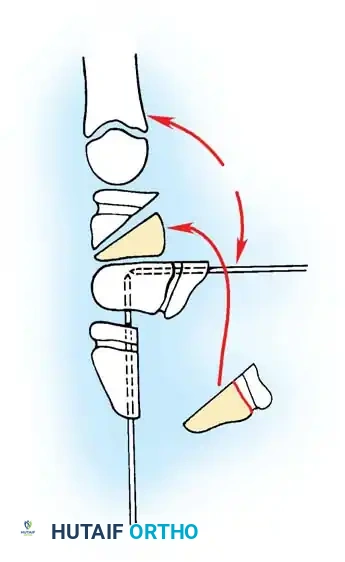

TECHNIQUE 76-52: Release of a Congenital Trigger Finger

Surgical management of a trigger finger requires a more extensile approach due to the high likelihood of complex FDS/FDP interactions.

- Extended Exploration (If Triggering Persists):

- Inspect the FDS tendon for a more proximal-than-normal decussation (chiasm of Camper) or an abnormal insertion into the FDP tendon.

- If an abnormal FDS slip is tethering the FDP, excise one or both slips of the FDS tendon to decompress the sheath.

- Inspect the A3 pulley. If triggering occurs at this level, carefully release the A3 pulley, ensuring the A2 and A4 pulleys remain strictly intact.

Intraoperative view demonstrating the excision of an abnormal FDS slip to relieve persistent triggering after A1 release.

Biomechanical illustration showing the relationship of the FDS and FDP tendons within the digital sheath.